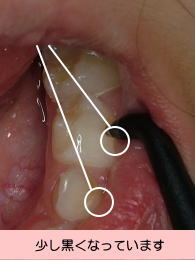

‚Þ‚µŽ•‚̃Œ[ƒU[‘ª’èŠíiƒ_ƒCƒAƒOƒmƒfƒ“ƒgj‚É‚æ‚è‚Þ‚µŽ•‚Ì’ö“x‚ð”’l‰»i‚O`‚X‚Xj‚µA‚Å‚«‚邾‚¯í‚ç‚È‚¢Ž¡—ÃiMI@ŬNPj‚ð‚µ‚Ü‚·B

ƒ{[ƒ_[ƒ‰ƒCƒ“‚ÌŽ•‚ÍAŽ•ƒuƒ‰ƒV‚ƃtƒb‘f“h•z‚Ì’èŠúŒŸf‚Å”’l‚Ì‘Œ¸‚ðŠm”F‚µ‚Ü‚·B